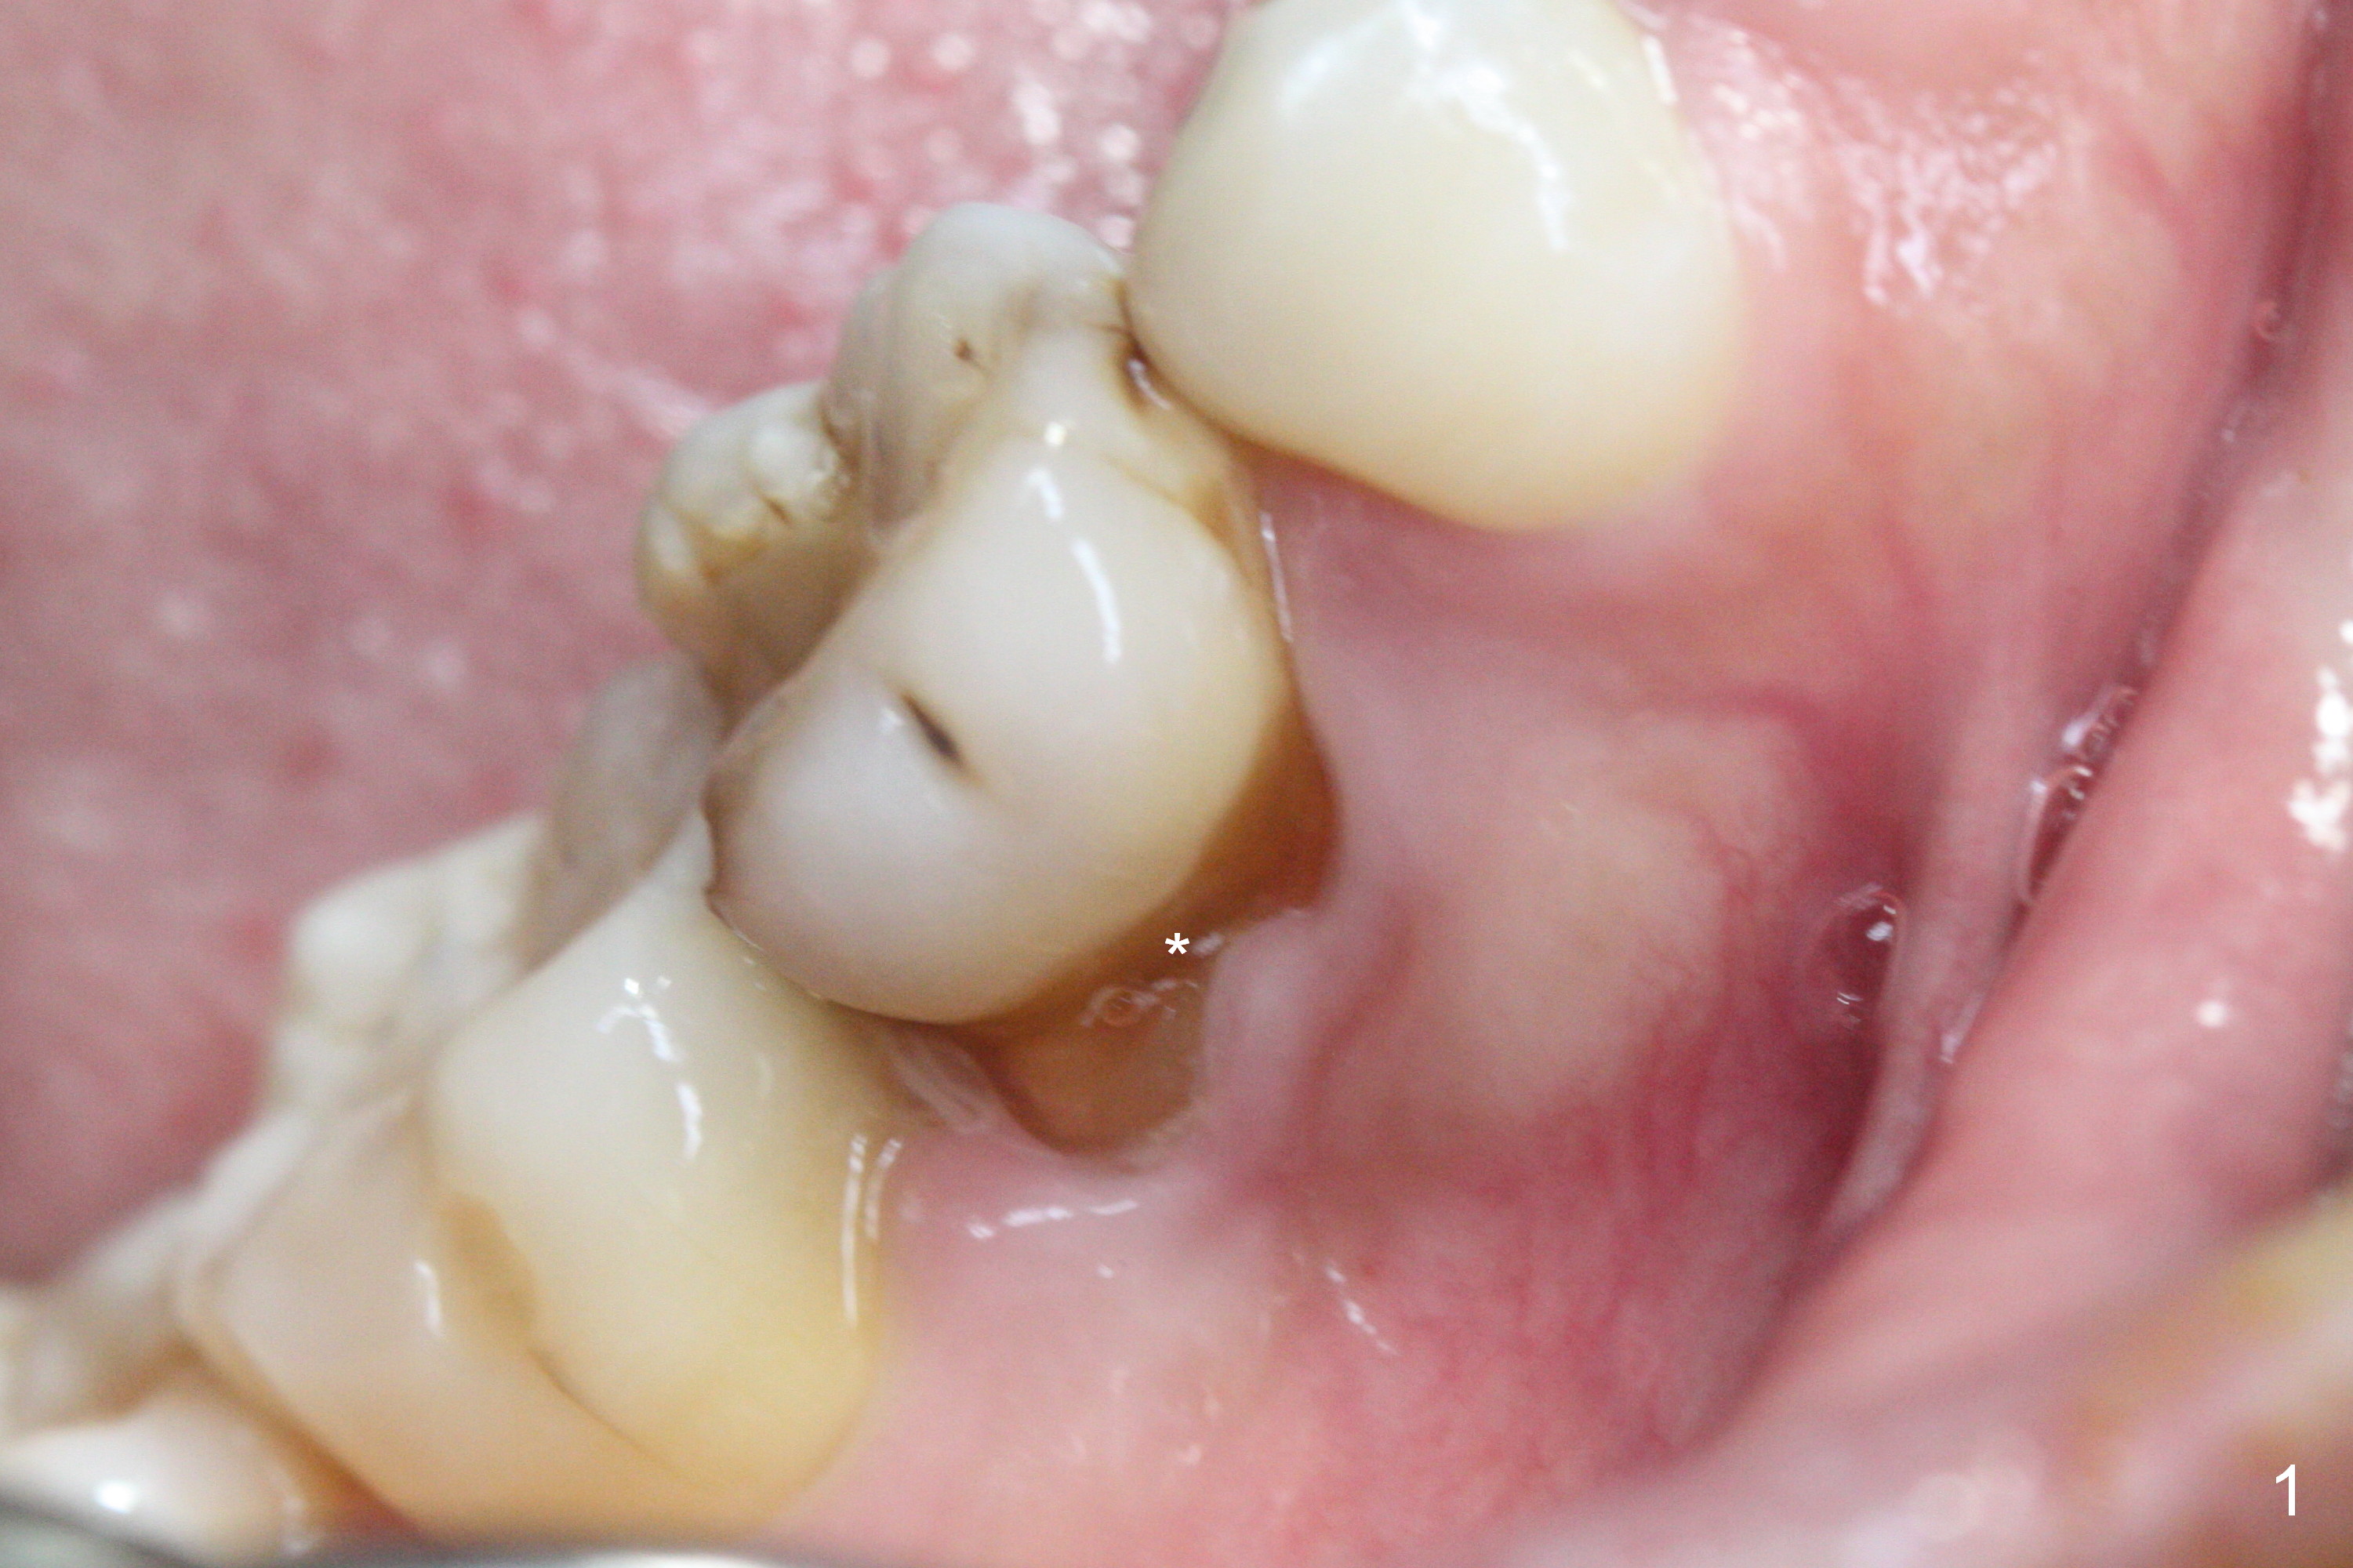

The lower 2nd primary molar has buccal furca lesion (Fig.1 *) with the thin buccal plate (Fig.2). Osteotomy is initiated in the sloped septum (Fig.3). After use of Magic Drill (MD) 3.3 mm for 13 mm and MD 3.8 mm for 11 mm, placement of a 4x11 mm IBS implant meets resistance because of the dense bone (Fig.4-6, red dashed line: Mental Loop) with final insertion torque >50 Ncm. After placement of a 6x4(3) mm abutment and autogenous bone in the remaining shallow sockets (Fig.6), a provisional is fabricated (Fig.7). Finally periodontal dressing is applied. Impression is taken 3 months postop (Fig.8). Buccal infection develops 2 weeks post cementation (Fig.9). When the crown/abutment is removed, there is no residual cement. The implant threads can be felt through the fistula. After soft tissue debridement and copious irrigation, Arestin is placed in the fistula. The latter disappears 15 days post debridement. The patient feels better and moves out of state. It appears that early periimplantitis develops because of the preexisting buccal furca lesion and failure to place the implant deep. The implant will be placed deep after loosening a little (since there is apical space (Fig.8 white line)) or removed, truncated at the apex and placed lower than the buccal crest.